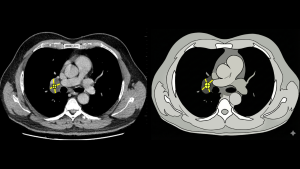

Fig 2: Axial CT (Left) and corresponding schematic (Right) demonstrate a cystic lesion centered in the right hilum. Applying the Center Method, the geometric epicenter localizes strictly to the Visceral Compartment. (Schematic illustration created with AI assistance (Gemini/Banana Pro) and manually refined)